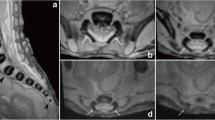

This study encompassed 55 human fetuses (27 males and 28 females) aged 17–30 weeks of white racial origin (Table 1), which had been derived from spontaneous abortions or stillbirths in the years 1989–2001 as a result of placental insufficiency. Gestational age was determined by the crown–rump length [13]. No attempt was done to encourage fetal donation. The use of the fetuses for research was approved by the University Research Ethics Committee (KB 275/2011). The fetuses included were free from visible external malformations. The entire material was immersed in 10 % neutral buffered formalin solution with ethanol added. After having been fixed in formalin, the fetuses underwent CT examinations with the reconstructed slice width option of 0.4 mm. As a consequence, 128 slices were acquired simultaneously by biograph mCT (Siemens). No bones showed evidence of abnormal development. The scans obtained were recorded in DICOM formats (Fig. 1a), which enabled us to compute three-dimensional reconstructions and the morphometric analysis of chosen objects. The gray scale of obtained CT images in Hounsfield units ranged widely, attaining the following values: from −275 to −134 for a minimum and from +1,165 to +1,558 for a maximum. As a result, the window width (WW) varied from 1,404 to 1,692, whereas the window level (WL) reached the values from +463 to +712. Such a wide WW, being characterized for osseous structures, enabled us both to estimate precisely the borders of each body ossification center of the spine and to determine accurate values for the parameters studied. DICOM formats were assessed by digital-image analysis of Osirix 3.9 (Fig. 1b), which semi-automatically calculated linear (sagittal and transverse diameters), two-dimensional (cross-sectional area), and three-dimensional (volume) parameters of the ossification center of C1–S5 vertebral bodies (Fig. 1c, d). The contouring procedure for each body ossification center was outlined with a cursor and stored.

The morphometric values obtained were characterized by normality of distribution (the Kolmogorov–Smirnov test) and homogeneity of variance (Levene’s test). No statistically significant differences were found in evaluating intra-observer reproducibility of the spinal measurements (P > 0.05, the one-way ANOVA test for paired data and post hoc RIR Tukey test). In addition, since no significant difference was observed in the values of the parameters studied according to sex (P > 0.05, Student’s t test), no attempt was made to further separate the results obtained according to sex (Table 2). By contrast, advancing gestational age was characterized by a statistically significant increase (P = 0.0000, the one-way ANOVA test for unpaired data and post hoc RIR Tukey test) in values of all measurements. Figure 2 presents the body ossification centers for C4, T6, and L3 in fetuses aged 18 (A), 21 (B), 25 (C), and 29 weeks (D).